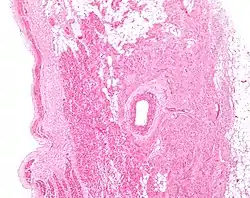

Figure 2: Low magnification stained image of the SA node (center-right on image) and its surrounding tissue. The SA node surrounds the sinoatrial nodal artery, seen as the open lumen. Cardiac muscle cells of the right atrium can be seen to the left of the node, and fat tissue to the right.

The cells of the SA node are spread out within a mesh of connective tissue, containing nerves, blood vessels, collagen and fat. Immediately surrounding the SA node cells are paranodal cells.[2] These cells have structures intermediate between that of the SA node cells and the rest of the atrium.[6] The connective tissue, along with the paranodal cells, insulate the SA node from the rest of the atrium, preventing the electrical activity of the atrial cells from affecting the SA node cells.[2] The SA node cells are smaller and paler than the surrounding atrial cells, with the average cell being around 8 micrometers in diameter and 20-30 micrometers in length (1 micrometer= 0.000001 meter).[7] Unlike the atrial cells, SA node cells contain fewer mitochondria and myofibers, as well as a smaller sarcoplasmic reticulum. This means that the SA node cells are less equipped to contract compared to the atrial and ventricular cells.[8]